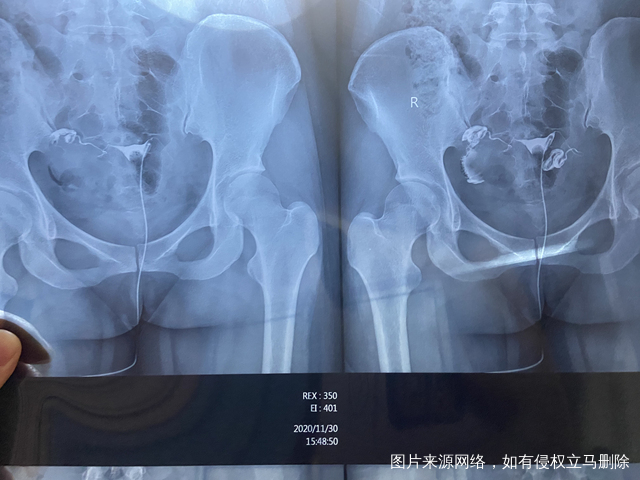

右侧腹股沟偶感疼痛备孕半年